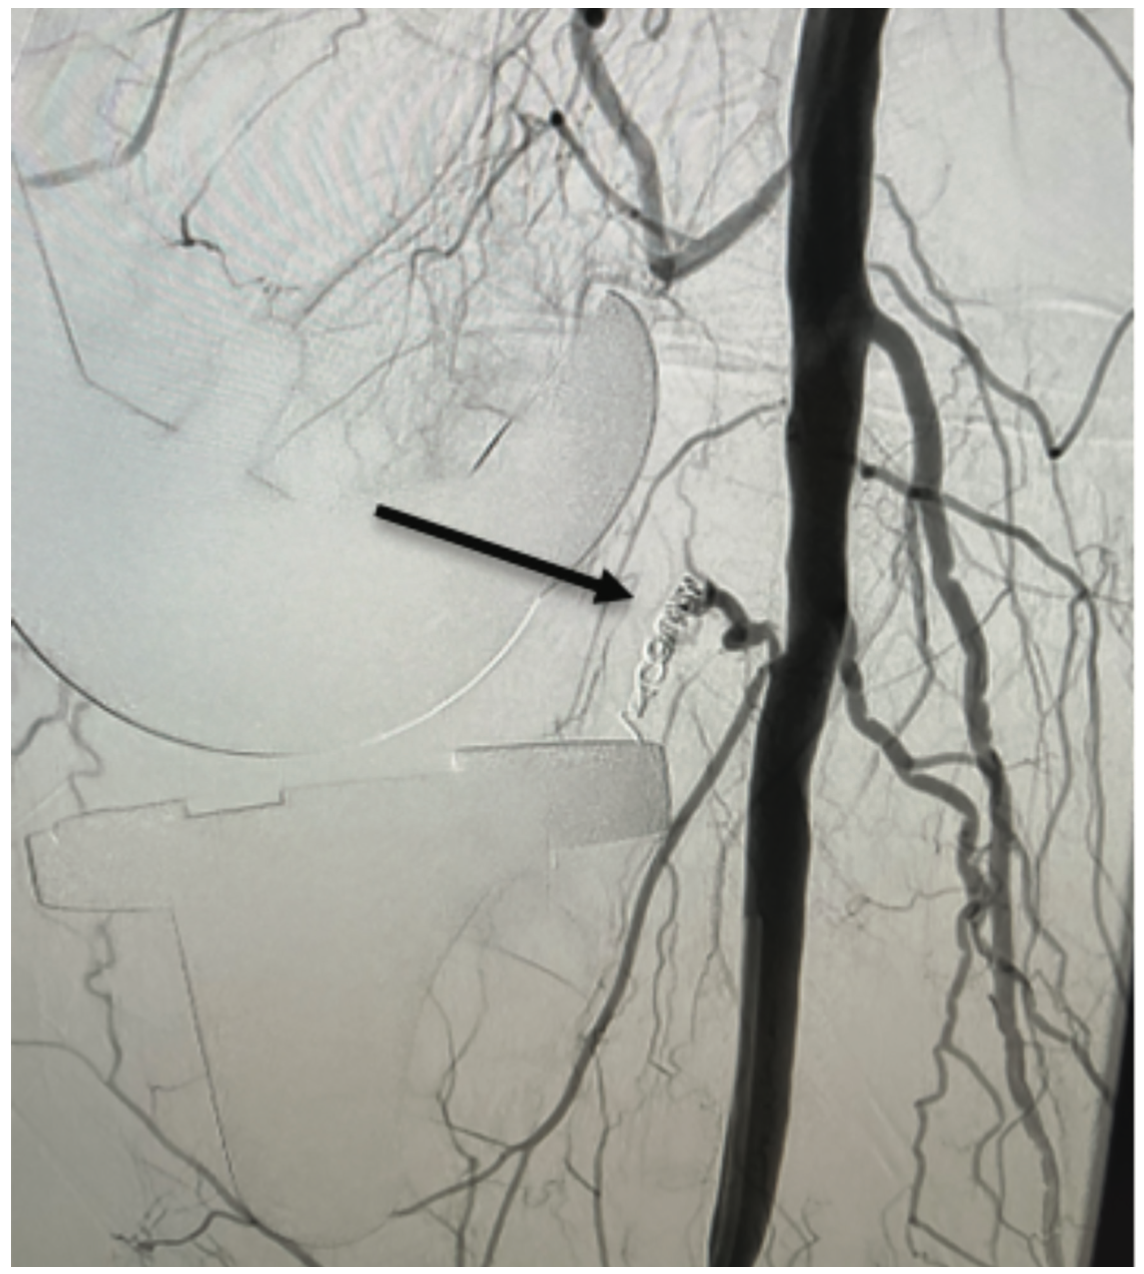

The left common femoral artery was accessed, the right external iliac artery was selectively engaged, and an angiogram was performed for delineation of the popliteal artery and its branches (Figure 2). Transpedal access was then obtained to the right anterior tibial artery for a better approach to the acute upward angle takeoff of the inferior genicular artery. A multipurpose catheter was then advanced to the level of the P2 segment of the popliteal artery. Using a combination of an .014 Advantage Glidewire (Terumo Interventional Systems) and Cantata Microcatheter (Cook Medical), the lateral inferior genicular artery was selected and the catheter was advanced to the intraluminal position. Two coils, a 2 mm x 7 mm Nester coil (Cook Medical) and then a 2 mm x 2 mm Nester coil, were deployed in standard fashion (Figure 3). Subsequent angiography showed successful coiling of the lateral inferior genicular branch. The microcatheter and multipurpose catheter were removed (Figure 4). Hemostasis was obtained using manual pressure for the right transpedal access and Angio-Seal (Terumo Interventional Systems) for the left femoral artery.